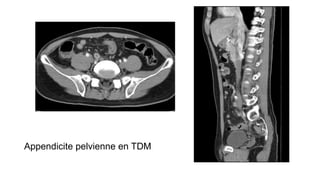

Appendicite pelvienne en TDM

Scanner pelvien avec injection

APPENDICITE

– Appendice de D> 6mm

– La paroi est épaissie et prise de

contraste

– Appendicolithe

– Infiltration de la graisse (péri cæcale,

pariétocolique)